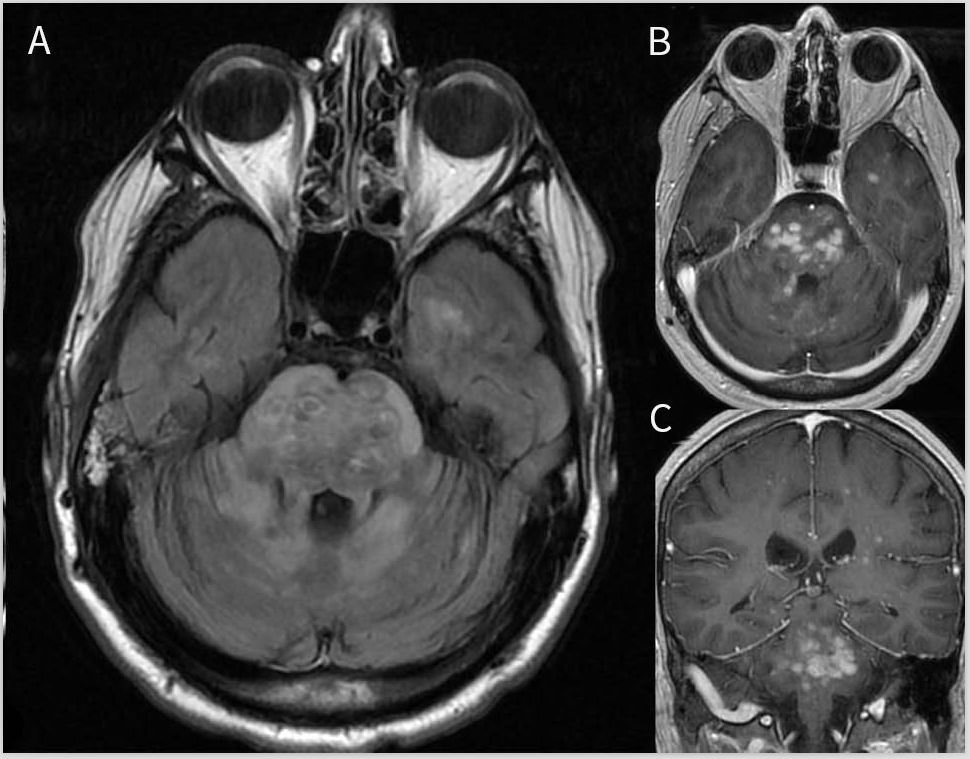

脑干受累,单独或与半球或脊髓疾病相结合,是NBD中最常见的实质表现。神经系统表现通常与诸如口腔溃疡、皮肤病变和发烧等有关。没有口腔溃疡病史的NBD极为罕见。急性发作期间最常见的MRI表现是孤立的、大的、不对称的、汇合的脑干上部病变(图3,C和D),其可能延伸到基底神经节区并横穿间脑。与MS相反,NBD病灶边缘模糊,并呈锯齿状;病灶常伴有水肿和增强,在缓解期间会消退或消失,很少表现为占位病变。脑干、基底神经节和内囊的边缘不清的病灶是较不常见的表现。弥漫性半球高信号病变也可见,常涉及脑室周围和皮质下深部白质。既往研究显示较在NBD急性期,ADC上的信号增加,即弥散增加,但也可在病灶中心看到小范围的弥散受限,提示坏死(图3,A和B),慢性过程会变成黑洞。在慢性或进展性病程中,脑干萎缩可能较明显,但仅在急性发作后12个月或更长时间的少数患者中可见。有学者提出脑干萎缩更支持NBD(相对于MS),尤其是在没有皮质萎缩的情况下。

图3 神经白塞病患者的MRI影像。弥散加权(A)成像和表观弥散系数(B)序列显示左侧内囊后肢中央弥散受限病灶。T2加权冠状位(C)和轴位(D)显示大的不对称性脑干右侧病灶延伸到小脑白质(箭头)。